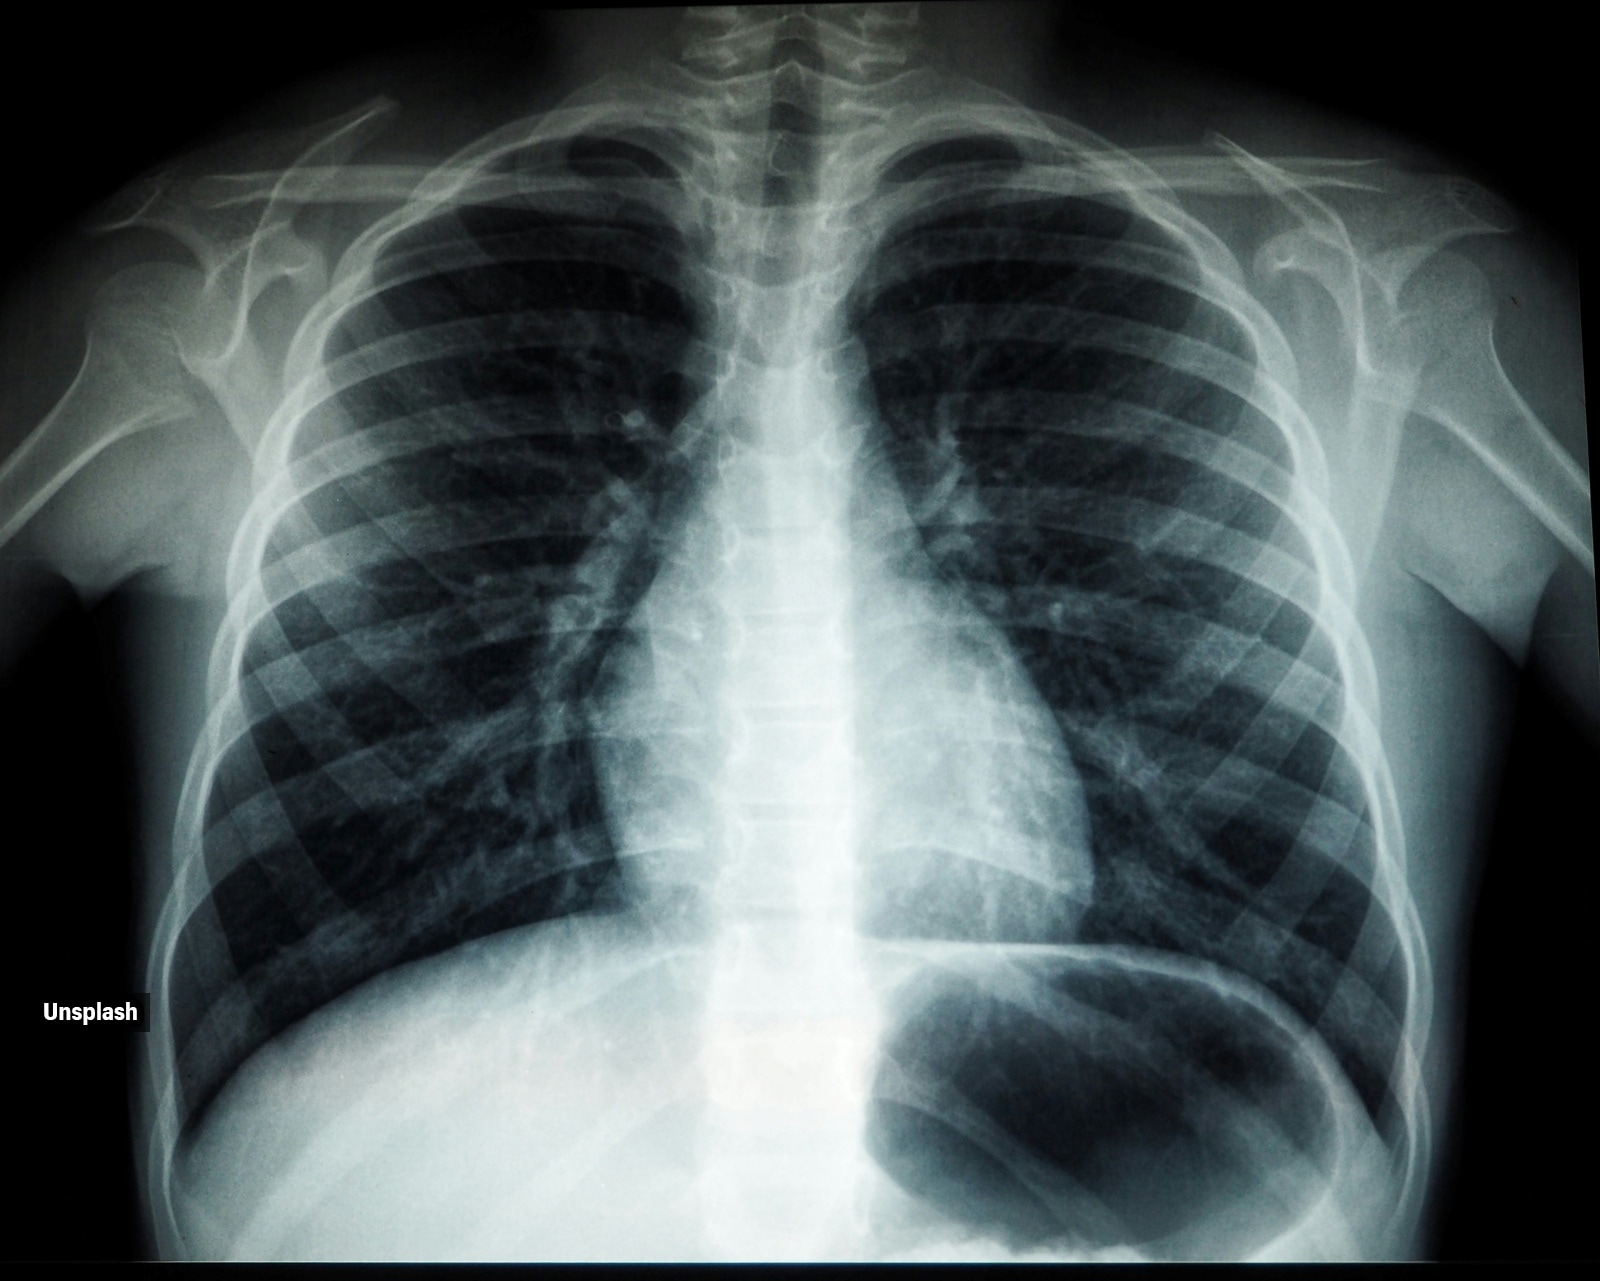

If brown phlegm persists, a chest X-ray may be done to check for infections or lung damage (Image: Unsplash)

- Chest X-ray to check for infections or lung damage